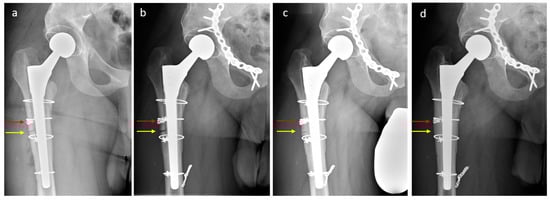

2.2. The Problem: Trochanteric Escape after ETO

2.2.2. Clinical Case

2.3. Novel Surgical Technique: A Monocortical Screw for Preventing Trochanteric Escape